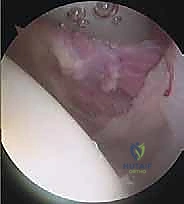

تثبيت الكتف الخلفي بالمنظار: دليل شامل لاستعادة الاستقرار مع الأستاذ الدكتور محمد هطيف

استعيد استقرار كتفك الخلفي مع الأستاذ الدكتور محمد هطيف في صنعاء. تعرف على أسباب عدم الاستقرار الخلفي، الأعراض، التشخيص، وخيارات العلاج بال…